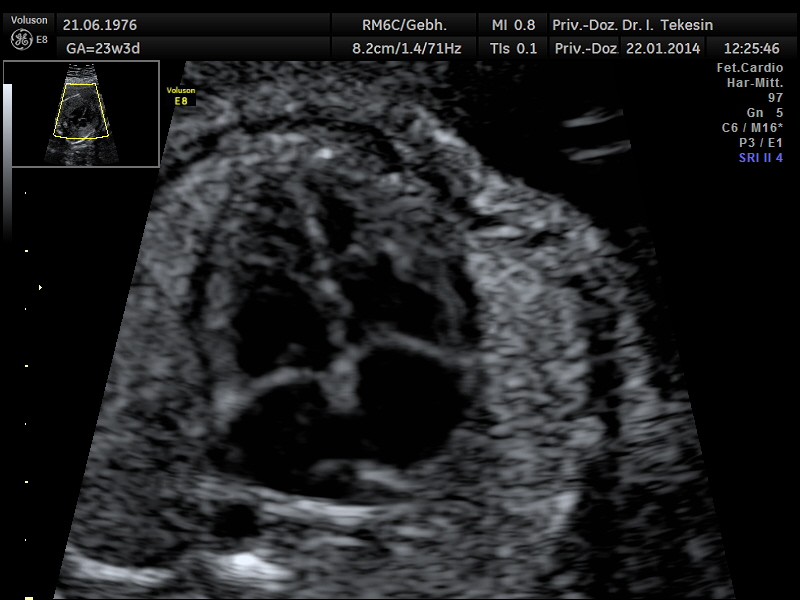

Fetale Echokardiographie

Ein weiterer Bestandteil der weiterführenden Ultraschall-Diagnostik ist die Beurteilung des kindlichen Herzens und der großen Blutgefäße, die fetale Echokardiographie. Dabei untersuchen wir die Lage, Größe und Symmetrie des Herzens, Anatomie der Herzstrukturen, Funktion der Herzklappen, Herzfrequenz und die Lage der großen Gefäße. Mit Hilfe der farbkodierten Doppler-Sonographie des Herzens werden weitere Details untersucht: die Funktion der Herzkammern, Herzscheidewände, Blutflüsse im Herzen und Blutflüsse in den großen Gefäßen.

Das Ziel dieser Ultraschalluntersuchung des fetalen Herzens ist der weitest mögliche Ausschluss von angeborenen Herzfehlern. Die Voraussetzung hierfür sind eine spezielle Ausbildung und Erfahrung des Arztes in Verbindung mit der hohen Qualität des Ultraschallgerätes.

Normaler Vierkammer-­‐Blick

Normaler Vierkammer-Blick